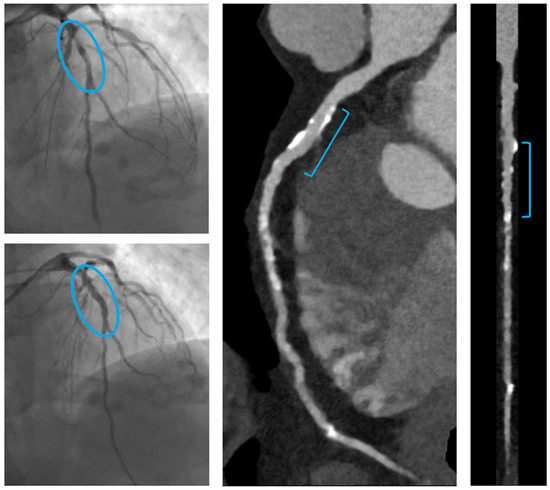

- C.

- A patient with a focal culprit plaque on the LAD, treated by one RMS (Magmaris® 2.5 × 25 mm).